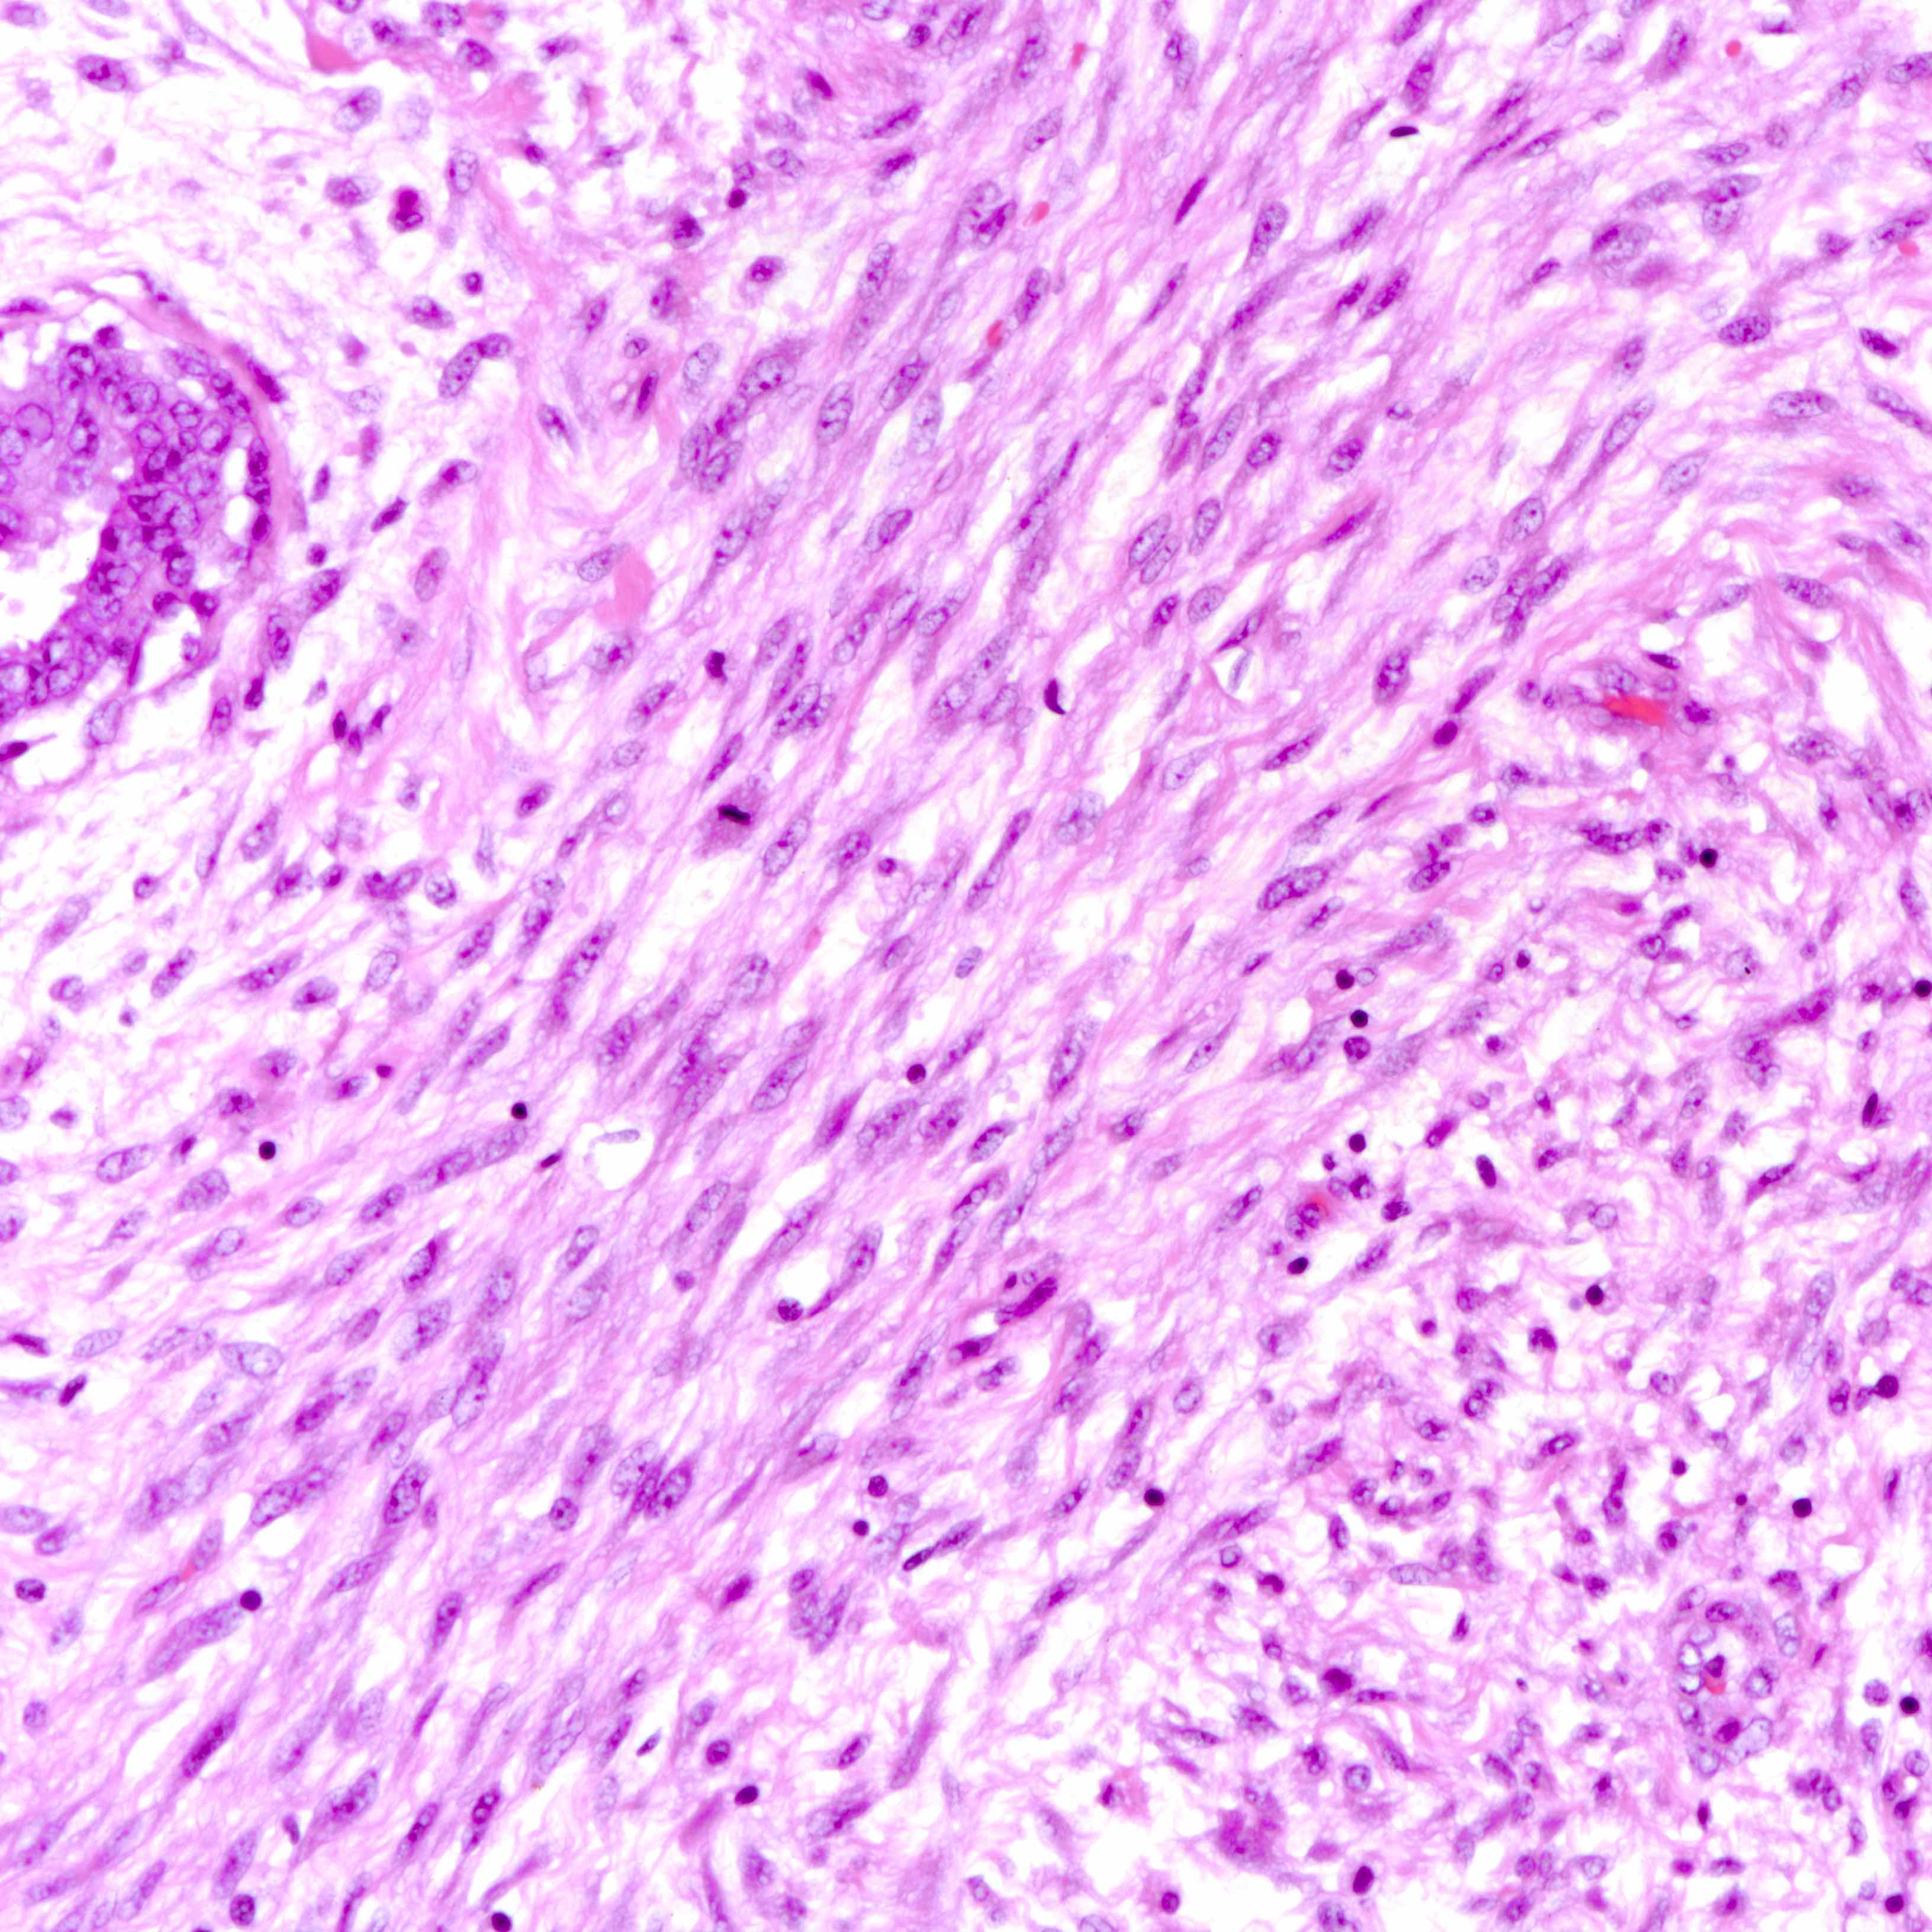

Microscopic (histologic) images

Contributed by Joshua J.X. Li, M.B.Ch.B. and Gary M. Tse, M.B.B.S.

Benign phyllodes tumor